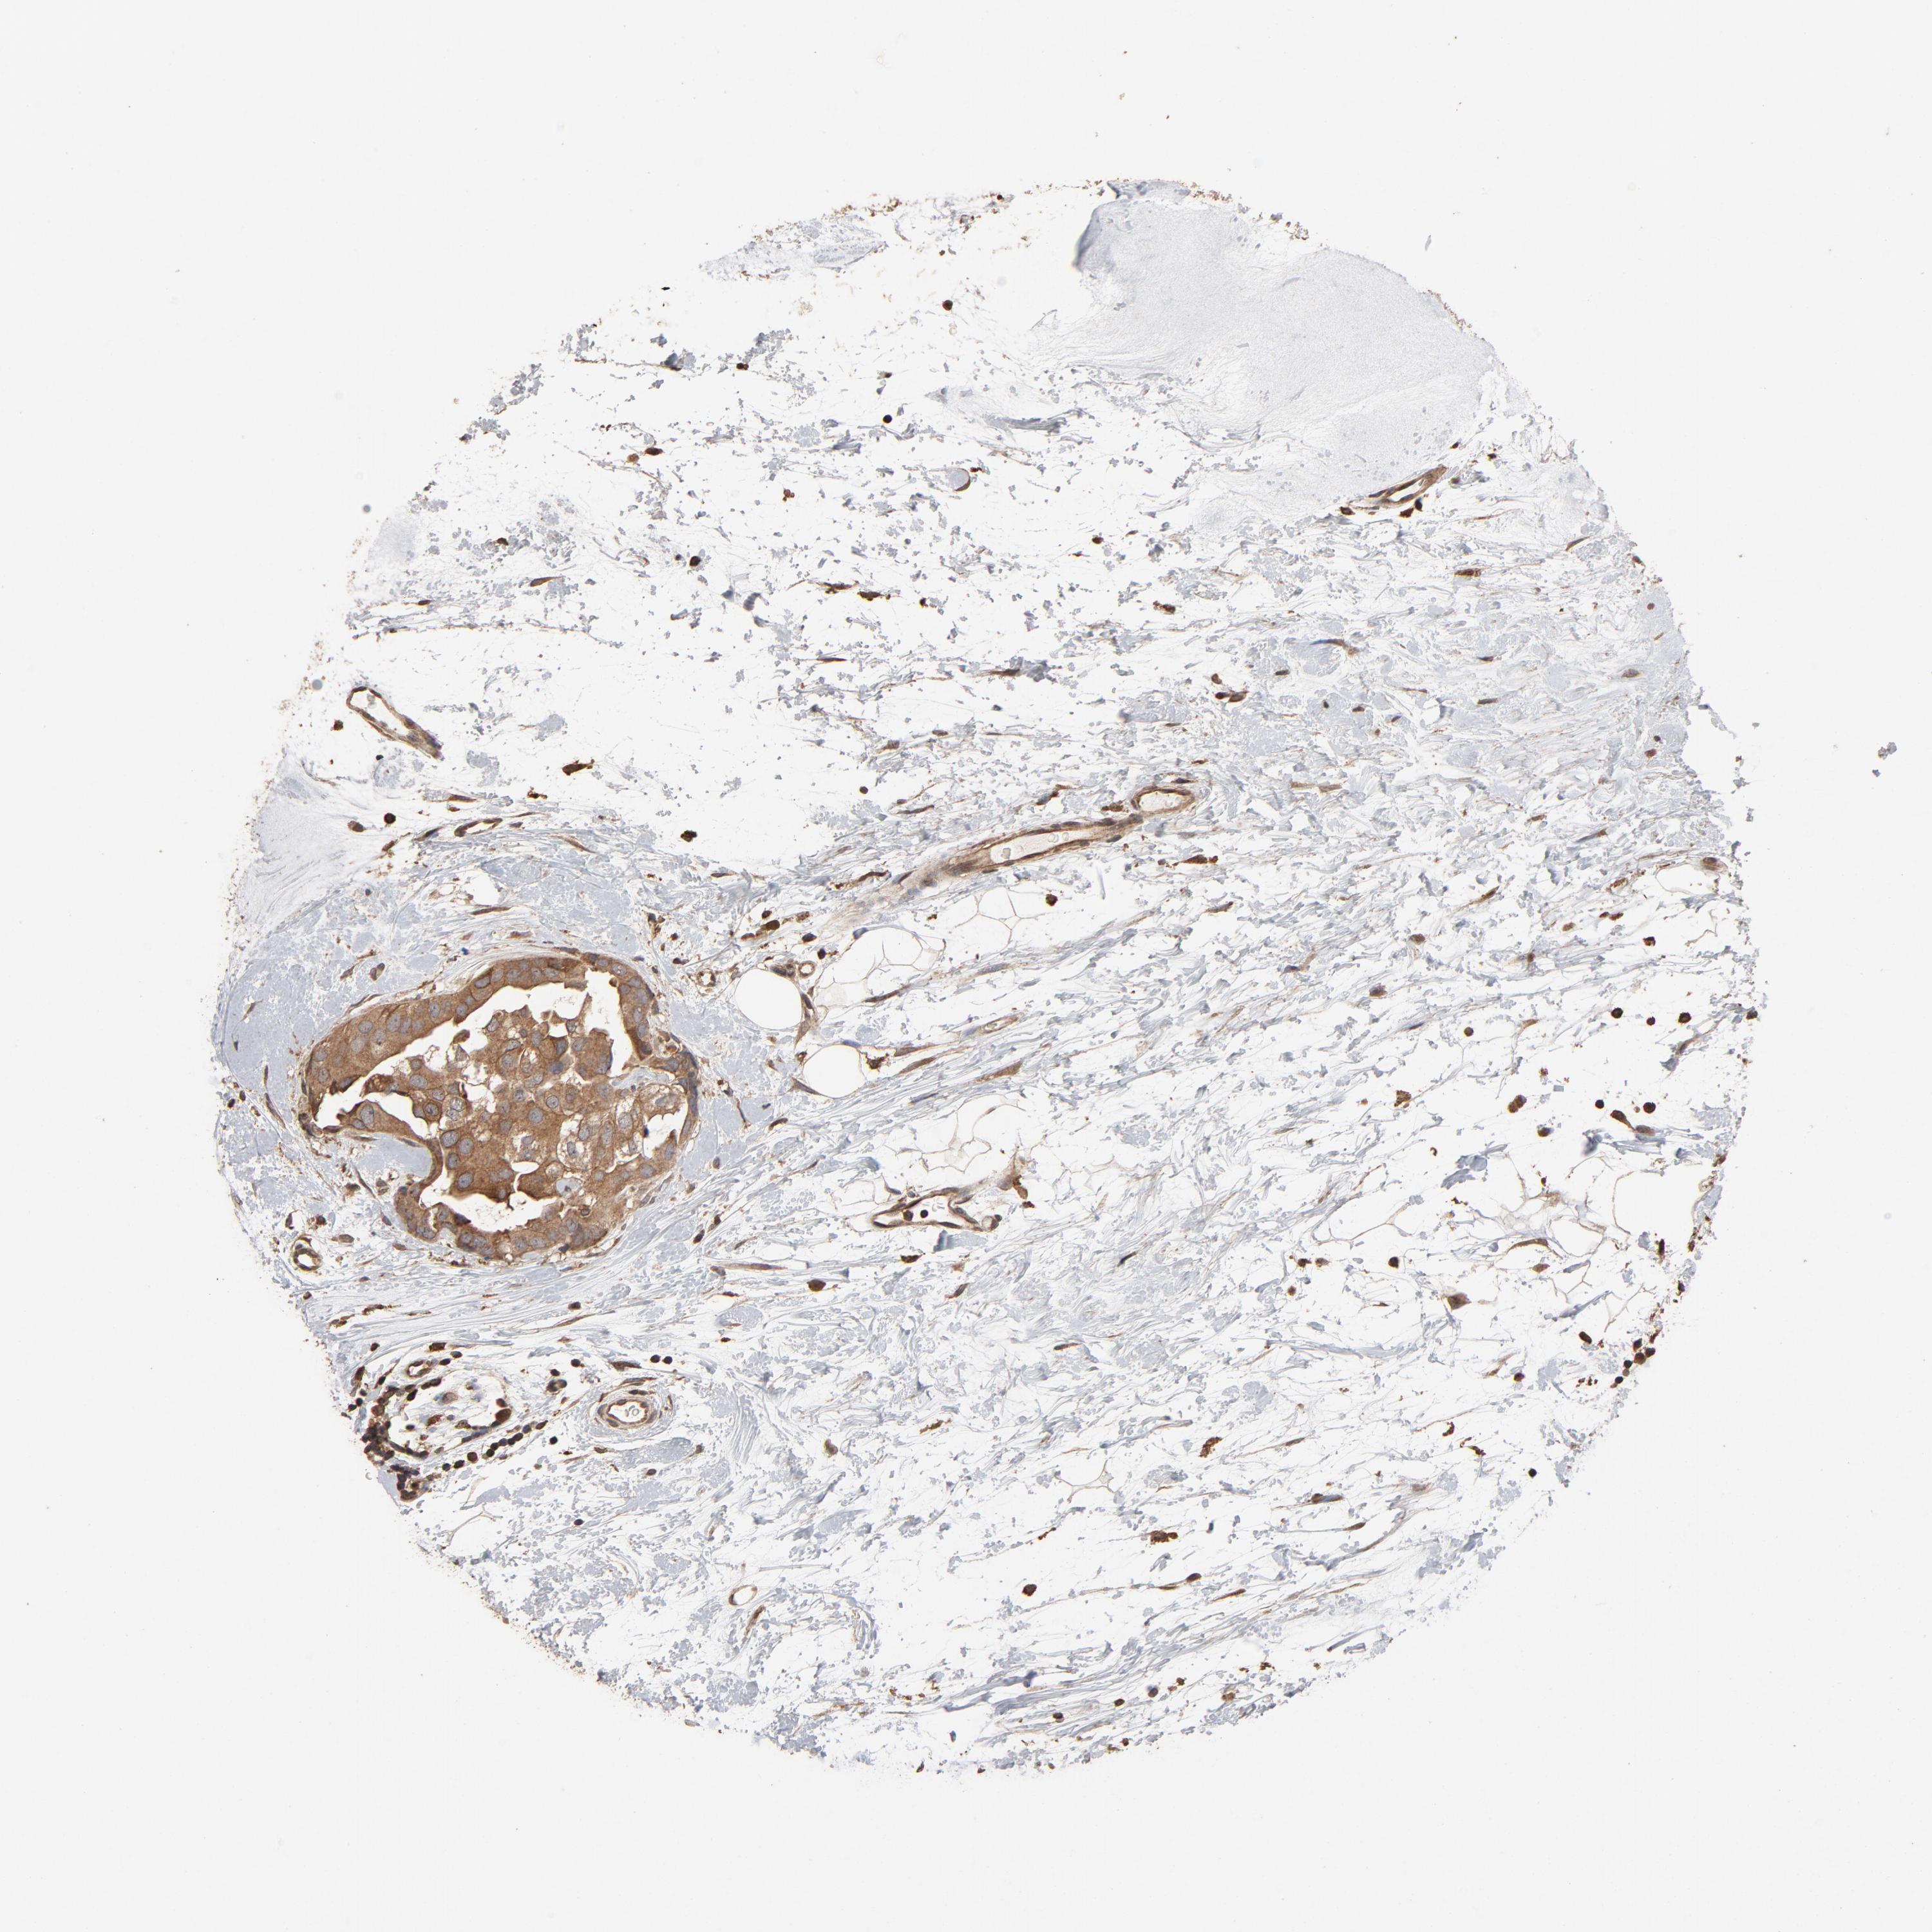

CDC42

CANCER BREAST CANCER Show tissue menu

BRCA TCGA BRCA VALIDATION PROTEIN EXPRESSION